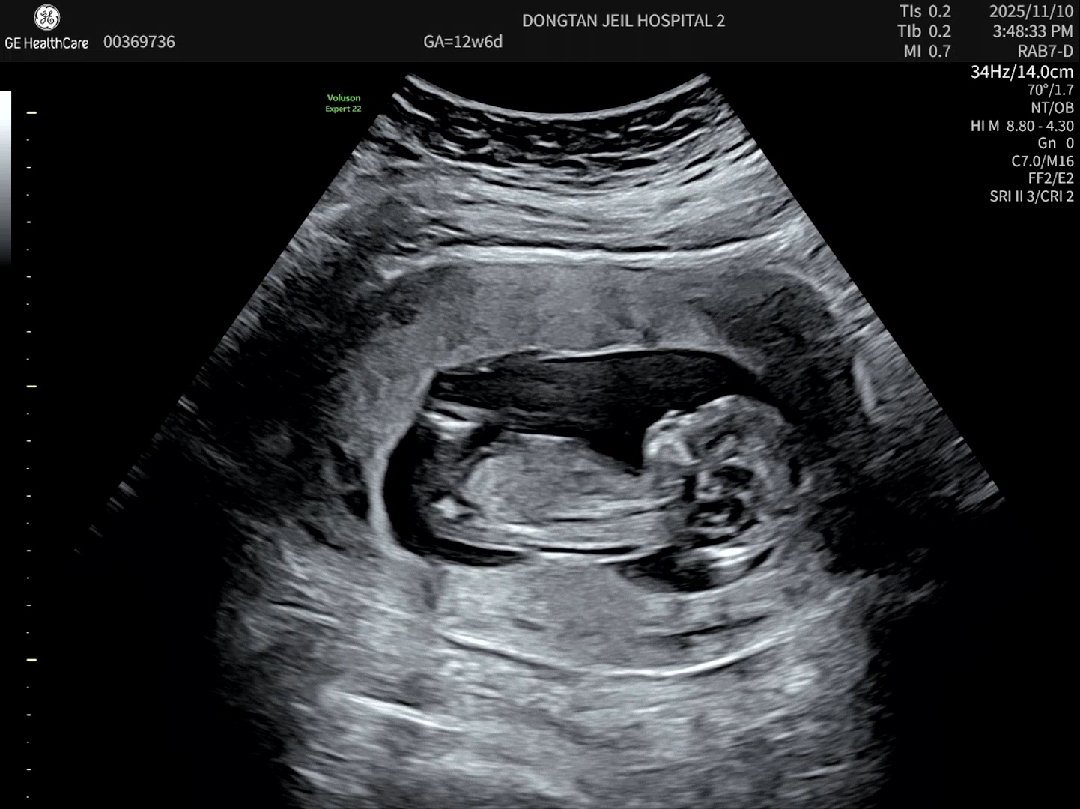

아무리봐도 각도법을 모르겠어요.. 12주6일차, 목투명대는 정상이고 니프티결과 대기중인데 다리사이로는 뭐 안보이더라구요😂 각도법으로 성별구분한다는데 저는 봐도 모르겠어요 혹시 다른 맘들이 보기에 어떤지 궁금해요!! 딸일것같나요? 아들일것 같나요?ㅎㅎ